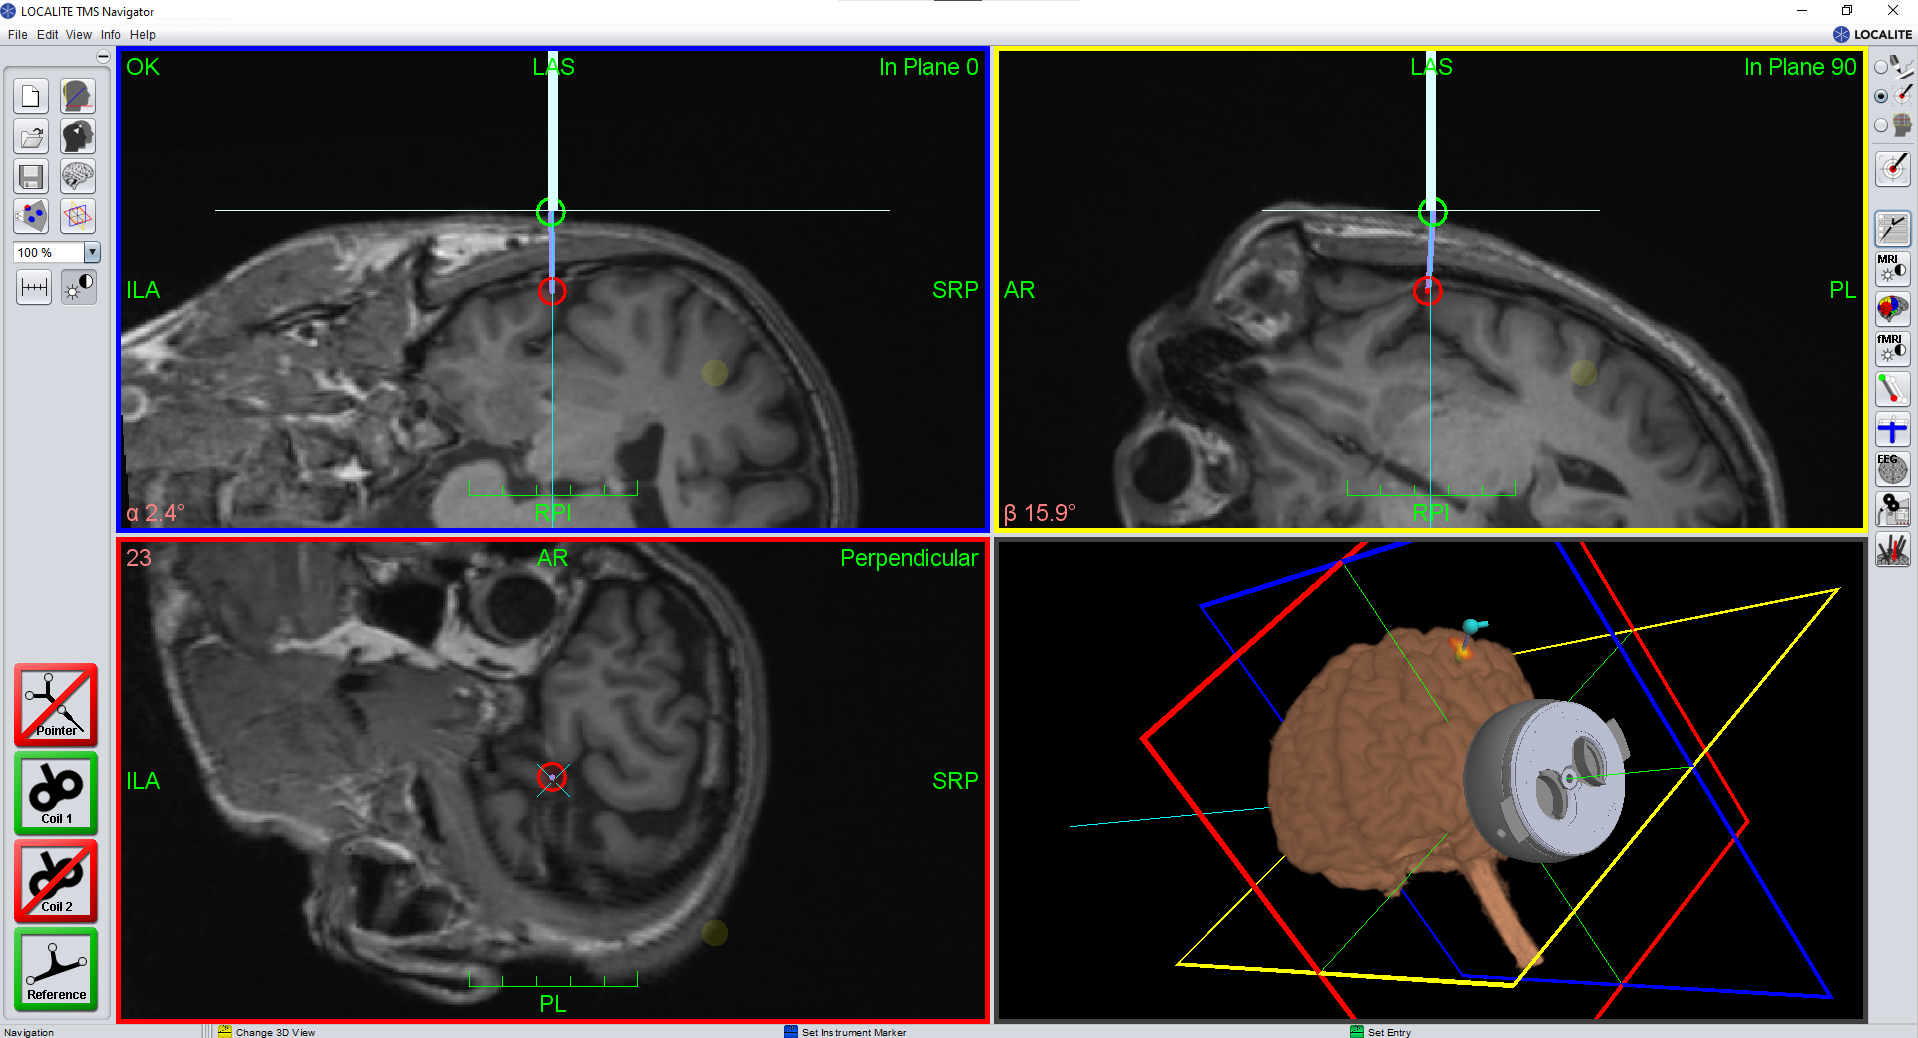

Soterix Medical tFUS + BrainSight

Soterix Medical 的 BrainSonix tFUS 系統可與 BrainSight 導航系統配對,提供完全整合的導航解決方案。